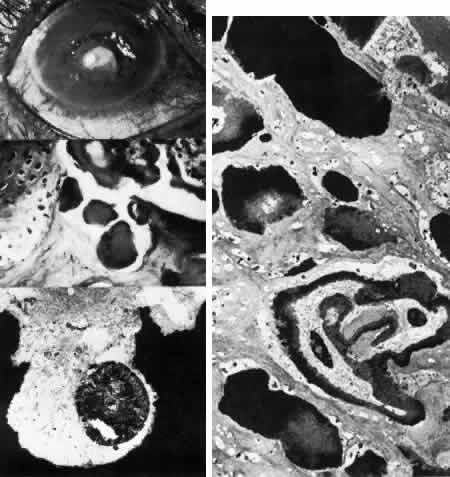

Macular Dystrophy (Groenouw Type II)

Among the classic corneal dystrophies, macular dystrophy, unlike granular and lattice dystrophies, is an autosomal recessive disorder and is far less common. It usually begins in the first decade of life and leads to progressive visual deterioration as the stroma becomes generally cloudy, with superimposed dense, gray-white spots (Figs. 5 AND 11; Color Plate 1H). Unlike granular dystrophy, these macular spots have indefinite edges and the intervening stroma is not clear. Young patients exhibit axial lesions in the superficial layers of the cornea, but with time, lesions approach the periphery and extend throughout the entire stromal thickness. Corneal thinning confirmed by central pachymetry has been documented.129 Also unique is primary involvement of the endothelium as evidenced clinically by the presence of guttate changes of Descemet's membrane.

Fig. 11. Macular corneal dystrophy. Top left. Clinical appearance of cornea features diffuse haze extending to the limbus with superimposed, dense gray-white spots. Bottom left. Light photomicrograph of posterior cornea shows endothelial cells staining intensely positive for acid mucopolysaccharide. Guttate excrescences (*) of Descemet's membrane (DM) are frequent. The stroma also shows positive staining for acid mucopolysaccharide both diffusely extracellularly and intensely within keratocytes (circled) (colloidal iron × 500). Right. Transmission electron micrograph discloses typical fibrillary granular deposits within keratocytes (K), throughout the posterior layer of Descemet's membrane, and within the endothelial cells (En). The anterior banded region of Descemet's membrane (bracketed) is not affected (× 3500).

The lesions in macular corneal dystrophy stain intensely with alcian blue and colloidal iron, minimally with PAS, and not at all with Masson's trichrome. Birefringence is decreased. The lesions have been histochemically identified as an abnormal keratan sulfate-like glycosaminoglycan that accumulates extracellularly within the stroma and Descemet's membrane and intracellularly within keratocytes and endothelium.130

As would be typical of an autosomal recessively inherited condition, macular dystrophy presumably results from deficiency of a hydrolytic enzymes (sulfotransferase) and may thus be considered a localized mucopolysaccharidosis.131 The effect of altered glycosaminoglycan metabolism is evident at the cellular level; on transmission electron microscopy, keratocytes and endothelial cells exhibit distention of rough-surfaced endoplasmic reticulum cisternae. With the acridine orange technique, compensatory generalized hyperactivity of the lysosomal enzyme system has been demonstrated.132 Eventually the accumulated undigested storage products engorge the cells, and the cells ultimately degenerate or rupture. The derivation of these intracytoplasmic storage vacuoles from endoplasmic reticulum suggests that the biochemical lesion in macular dystrophy occurs at a different metabolic location than in the systemic mucopolysaccharidoses, since in the latter, storage products accumulate within lysosomelike intracytoplasmic vacuoles associated with the Golgi complex.133 Snip and associates134 were able to determine that the storage phenomenon affecting endothelium and Descemet's membrane is likely also primary, since the intracellular and extracellular lesions appear ultrastructurally comparable to those evident in the keratocytes and stroma.

Two subtypes of macular dystrophy have been immunohistochemically identified. Type I is most prevalent and is characterized by the absence of antigenic keratan sulfate in the cornea as well as in the serum; it, in fact, may represent a more widespread systemic disorder of keratan sulfate metabolism.135 In type 2, antigenic keratan sulfate is present in both cornea and serum.

The treatment for macular dystrophy is corneal transplantation. Recurrence in the graft has been reported.119,136